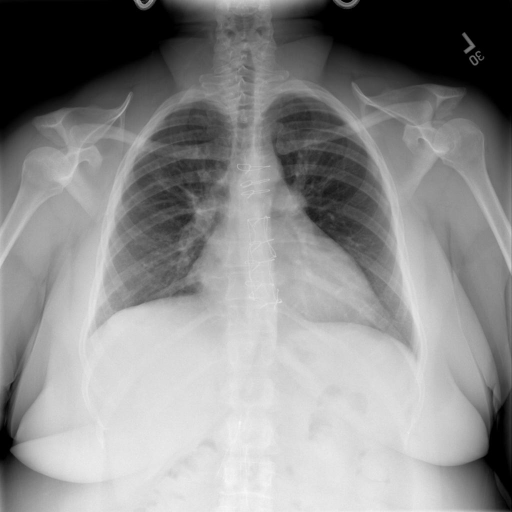

# 本文贡献  - 借助ChatGPT以及公开的数据集,我们构造了一个`X光影像-诊断报告`对的医学多模态数据集; # 数据集 - [MIMIC-CXR](https://physionet.org/content/mimic-cxr-jpg/2.0.0/)是一个公开可用的胸部X光片数据集,包括377,110张图像和227,827个相关报告。 - [OpenI](https://openi.nlm.nih.gov/faq#collection)是一个来自印第安纳大学医院的胸部X光片数据集,包括6,459张图像和3,955个报告。 在上述工作中,报告信息都为非结构化的,不利于科学研究。为了生成合理的医学报告,我们对两个数据集进行了预处理,并最终得到了可以用于训练的**英文报告**。除此之外,为了更好的支持中文社区发展,借助ChatGPT的能力,我们将英文报告进行了中文翻译,并最终形成了可用于训练的数据集。 |数据集|数量|下载链接| |:-|:-|:-| |MIMIC-CXR-zh|-|-| |OpenI-zh|6,423|[诊疗报告](./data/Xray/openi-zh.json) 、[X光影像](https://pan.baidu.com/s/13GBsDMKf6xBZBSHpoWH_EA?pwd=k9sh)| # 快速上手 1. 安装环境 ```bash # 安装依赖 pip install -r requirements.txt # 国内换源安装依赖 pip install -i https://mirrors.aliyun.com/pypi/simple/ -r requirements.txt ``` 此时默认会安装`deepspeed`库(支持`sat`库训练),此库对于模型推理并非必要,同时部分`Windows`环境安装此库时会遇到问题。 如果想绕过`deepspeed`安装,我们可以将命令改为: ```bash # 安装依赖 pip install -i https://mirrors.aliyun.com/pypi/simple/ -r requirements_wo_ds.txt # 安装SwissArmyTransformer pip install -i https://mirrors.aliyun.com/pypi/simple/ --no-deps "SwissArmyTransformer>=0.3.6" ``` 2. 模型推理 CLI推理: ```python python cli_demo.py --from_pretrained checkpoints/finetune-XrayGLM-05-25-01-04 --prompt_zh '详细描述这张胸部X光片的诊断结果' ``` 更多[参数](https://github.com/WangRongsheng/XrayGLM/blob/main/cli_demo.py#L16) # 效果展示 诊断: |X光影像|诊疗报告(医生)|XrayGLM| |:-|:-|:-| ||根据X射线图像,心脏大小正常,肺部看起来很清晰。已经排除了肺炎、积液、水肿、气胸、腺病、结节或肿块的存在。该发现表明一切正常。换句话说,总体印象是胸部正常。|X光片显示,心脏大小正常。肺部没有气胸或胸腔积液的证据。骨骼结构看起来没有任何异常。总的来说,X光片表明没有发现急性心肺疾病的迹象。| ||X光图片显示没有扭曲的区域、可疑的骨质不透明度或胸腺积液。心脏大小轻微增大,但非常稳定。此外,没有气胸的证据,肺野也正常。总体来说,X光片显示没有急性心脏异常,但要注意轻微的心脏扩大。|X光片显示,心脏大小正常。肺部和纵隔轮廓清晰,没有气胸或胸腔积液的证据。骨骼结构完整,没有任何急性异常。| ||心影形态在正常范围内。没有急性骨质异常。有可能出现没有明显的吸水或肺实质状况的线索。没有大面积积液或气胸。有可能怀疑其有误吸或肺实质问题。为了确诊和治疗,可能需要进行适当的影像学随访。|心脏大小正常,肺部和纵隔轮廓清晰。没有急性异常或活动受限的证据。没有任何明显的气胸、胸腔积液或肺不张的迹象。此外,也没有发现任何局灶性骨质异常或其他急性疾病。| 多轮对话: |X光影像|诊疗报告(医生)| |:-|:-| ||右侧主动脉突出观察到。心脏大小正常。胸部未发现明显的肺气肿、胸膜积液或可疑的肺部病变。报告指出已知右侧主动脉情况正常。| ```bash >> X光影像路径:./data/Xray/861_1.png >> 用户:这是一张什么图? >> XrayGLM:这张图片显示的是一张肺部检查的X光片。 >> 用户:请描述这张胸部X光片的诊断结果 >> XrayGLM:心脏大小正常,肺部清晰。没有急性心肺疾病的证据。 >> 用户:是否存在肺气肿? >> XrayGLM:没有肺气肿。心脏大小正常,肺部清晰。没有发现急性心肺疾病的证据。 >> 用户:平时饮食该注意什么? >> XrayGLM:饮食应该健康,均衡。建议增加蛋白质的摄入量,因为蛋白质有助于维持肌肉和骨骼的健康。多食用蔬菜、水果、全谷物以及健康的脂肪来源如橄榄油、鱼类等可以帮助获得足够的维生素和矿物质。此外,避免过度饮酒或吸烟,这些习惯可能会对心脏健康产生负面影响。 ``` # 项目致谢 1. [VisualGLM-6B](https://github.com/THUDM/VisualGLM-6B)为我们提供了基础的代码参考和实现; 2. [MiniGPT-4](https://github.com/Vision-CAIR/MiniGPT-4)为我们这个项目提供了研发思路; 3. ChatGPT生成了高质量的中文版X光检查报告以支持XrayGLM训练; 4. [gpt_academic](https://github.com/binary-husky/gpt_academic)为文档翻译提供了多线程加速; 5. [MedCLIP](https://github.com/RyanWangZf/MedCLIP) 、[BLIP2](https://huggingface.co/docs/transformers/main/model_doc/blip-2) 、[XrayGPT](https://github.com/mbzuai-oryx/XrayGPT) 等工作也有重大的参考意义;  这项工作由[澳门理工大学应用科学学院](https://www.mpu.edu.mo/esca/zh/index.php)硕士生[王荣胜](https://github.com/WangRongsheng) 、[段耀菲](https://github.com/IsBaSO4) 、[李俊蓉](https://github.com/lijunrong0815)完成,同时这项工作受到[檀韬](https://scholar.google.com/citations?hl=zh-CN&user=lLg3WRkAAAAJ)副教授、[彭祥佑](http://www.patrickpang.net/)老师的帮助支持。 *特别鸣谢:[USTC-PhD Yongle Luo](https://github.com/kaixindelele) 提供了有3000美金的OpenAI账号,帮助我们完成大量的X光报告翻译工作 # 免责声明 本项目相关资源仅供学术研究之用,严禁用于商业用途。使用涉及第三方代码的部分时,请严格遵循相应的开源协议。模型生成的内容受模型计算、随机性和量化精度损失等因素影响,本项目无法对其准确性作出保证。即使本项目模型输出符合医学事实,也不能被用作实际医学诊断的依据。对于模型输出的任何内容,本项目不承担任何法律责任,亦不对因使用相关资源和输出结果而可能产生的任何损失承担责任。 # 项目引用 如果你使用了本项目的模型,数据或者代码,请声明引用: ```bash @misc{wang2023XrayGLM, title={XrayGLM: The first Chinese Medical Multimodal Model that Chest Radiographs Summarization}, author={Rongsheng Wang, Yaofei Duan, Junrong Li, Patrick Pang and Tao Tan}, year={2023}, publisher = {GitHub}, journal = {GitHub repository}, howpublished = {\url{https://github.com/WangRongsheng/XrayGLM}}, } ``` # 使用许可 此存储库遵循[CC BY-NC-SA](https://creativecommons.org/licenses/by-nc-sa/4.0/) ,请参阅许可条款。